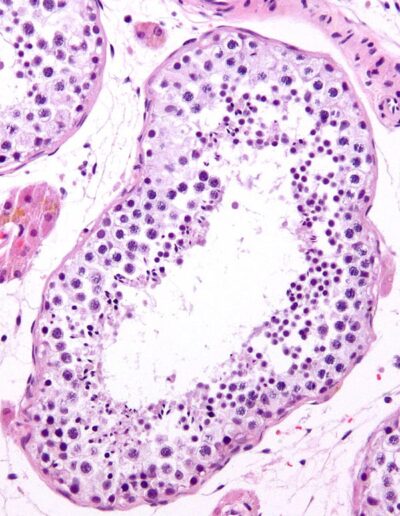

(1) Mikroskopisches Bild eines normalen Hodengewebe

Quelle: www.wikimedia.org

Licence: Permission is granted to copy, distribute and/or modify this document under the terms of the GNU Free Documentation

License, Version 1.2 or any later version published by the Free Software Foundation; with no Invariant Sections, no Front-Cover Texts, and no Back-Cover Texts. A copy of the license is included in the section entitled GNU Free Documentation License.

This file is licensed under the Creative Commons Attribution-Share Alike 3.0 Unported license.

Attribution: Nephron, CC BY-SA 3.0, via Wikimedia Commons. 07 Juni 2010.